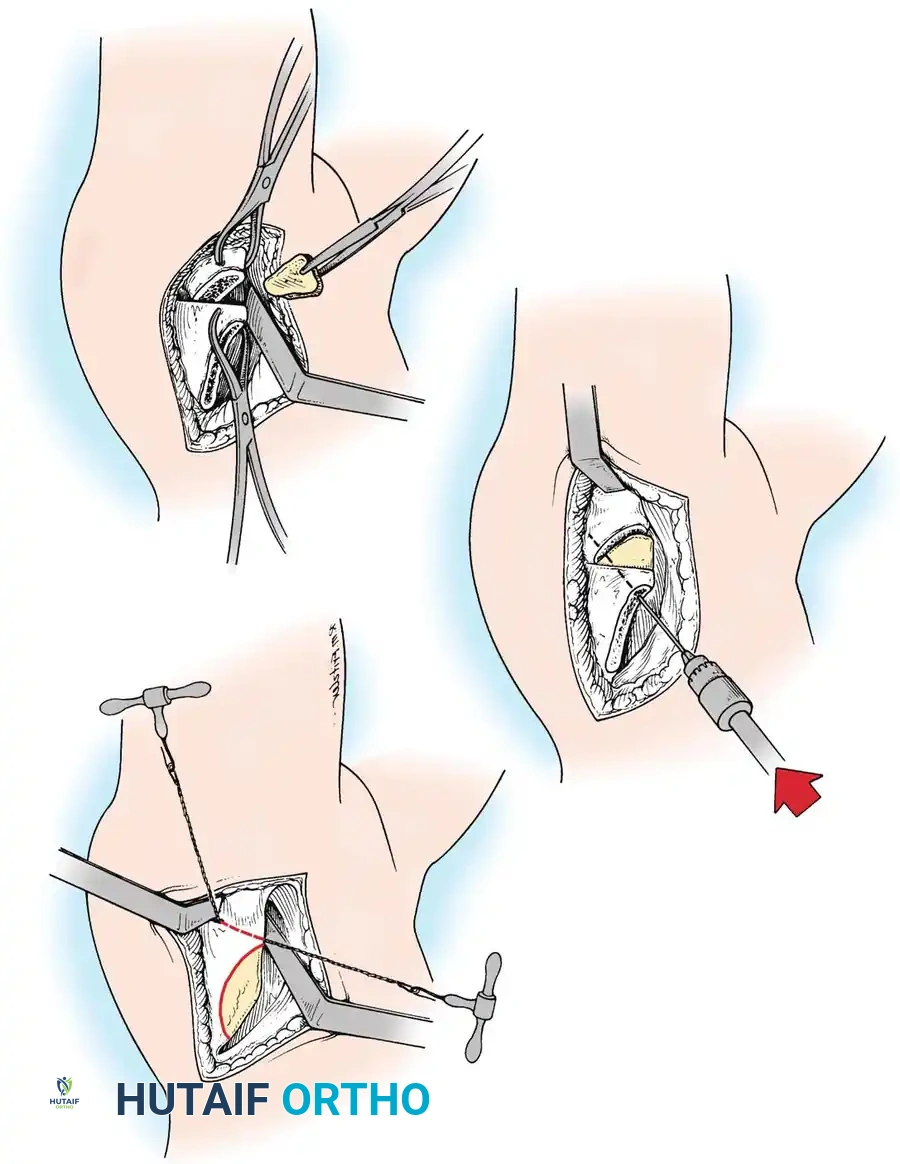

Intraoperative arthrogram demonstrating the cartilaginous contours of the femoral head and acetabulum during closed reduction.

Anterior Approach (Smith-Petersen):

1. Incision: "Bikini" incision below the iliac crest.

2. Interval: Develop the plane between the tensor fasciae latae (superior gluteal nerve) and the sartorius (femoral nerve).

3. Deep Dissection: Detach the rectus femoris from the AIIS. Isolate and release the iliopsoas tendon at the pelvic brim to relieve the hourglass constriction of the capsule.

4. Capsulotomy: A T-shaped or I-shaped capsulotomy is performed parallel to the acetabular margin.

5. Joint Clearance: Excise the ligamentum teres, clear the pulvinar, and incise the transverse acetabular ligament inferiorly. Never excise the limbus, as it is critical for future acetabular growth; radial incisions may be made if it is severely inverted.

6. Capsulorrhaphy: Following concentric reduction, the redundant capsule is advanced superiorly and laterally to stabilize the joint.

Intraoperative view of the anterior approach to the hip, demonstrating capsulotomy and exposure of the dysplastic joint.